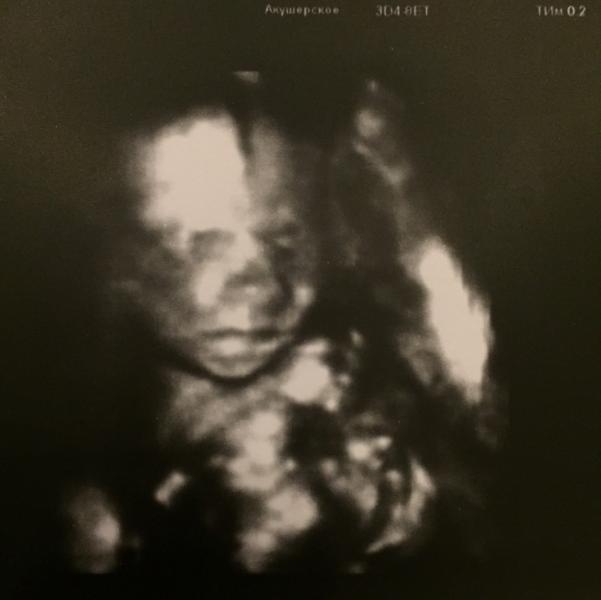

@lyus, @irusik1 ходила вчера на 3Д, не получилось сделать фото с личиком. Фото с личиком можно сделать если у вас будет послушный ребенок в это время. Наша мадам закрывала руками лицо, и била в аппарат. В итоге 30 минут пытались хоть как-то сфотографировать, так и не получилось. Черно белые фото это не 3Д, они должны быть оранжево-коричневые. А 4Д это видео.

Как хорошо видно!! Класс)) может и нам не терпеть до 28 недель и сделать 3д))! Так классно!! Надеюсь все у вас хорошо будет!!

@lyus, лучше позже сделать. В недель 25-28. Сказали ребёночек ещё маленький. Личико ещё не округлилось. Я пошла в основном чтобы дочке показать братика и шейку глянуть. Потому что не ясно смогу ли позже сделать 3д УЗИ.